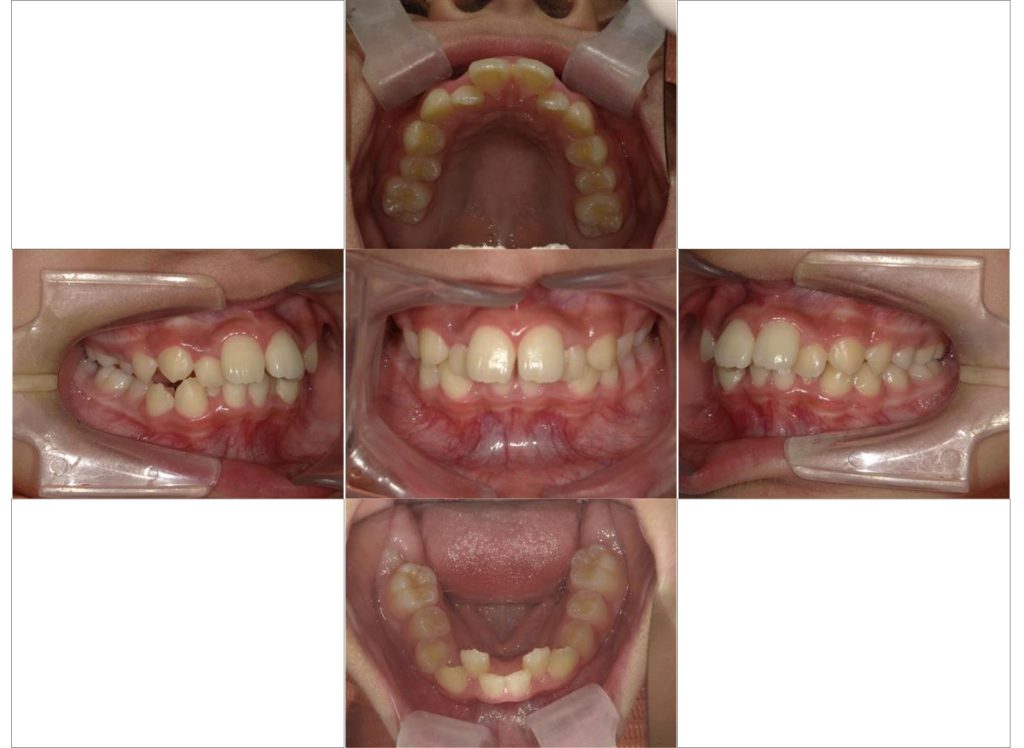

患者さんは10代の女性、前歯が出ていることが主訴になります。

お口の中の状態としては、上下の前歯の重なりが強く上の前歯が前方に、下の前歯が後方に傾いている状態でした。

今回は上下の歯列の拡大とそれによって生じたスペースを利用して重なりのある前歯の重なりを取り除いています。

矯正にかかった期間は2年間、歯の移動の中で上下の12歳臼歯の萌出も起こったのでコントロールを行いながらの治療となります。